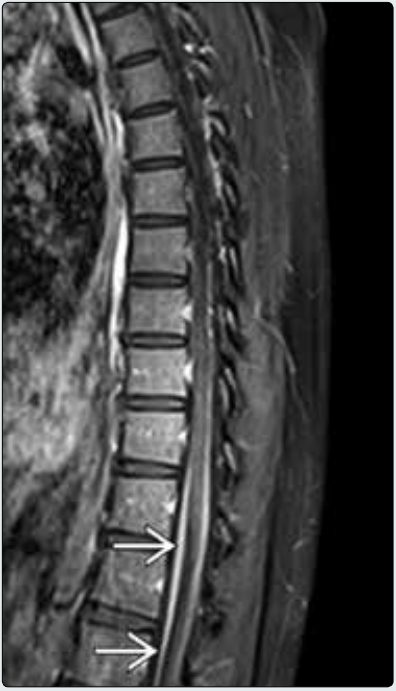

胸椎MR矢状位增强T1WI脂肪抑制显示马尾光滑线样增厚和强化→,该患者表现为典型急性发作性四肢远端无力、反射消失